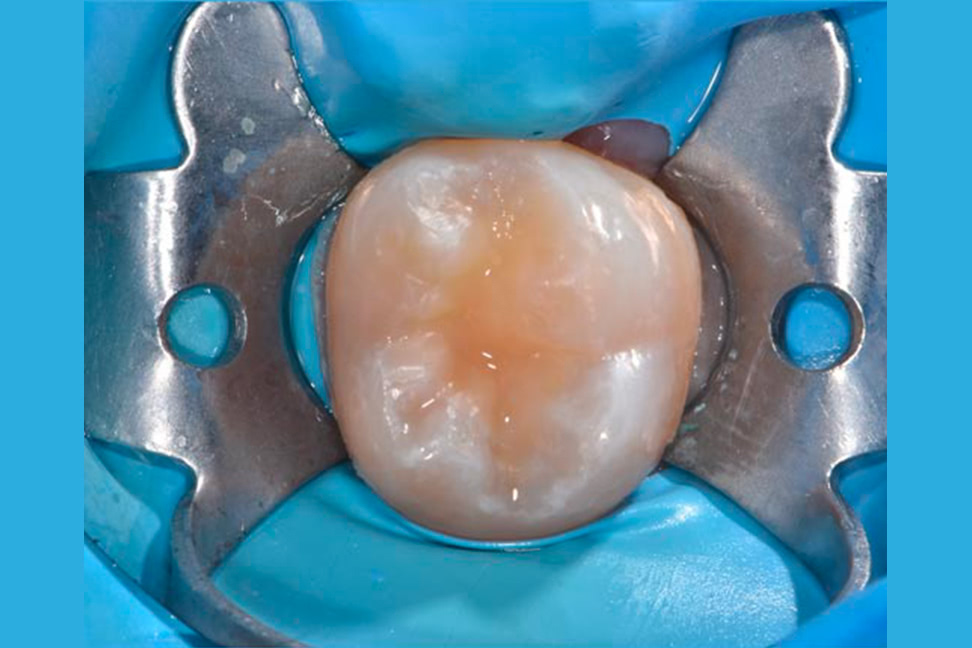

La carie è una malattia degenerativa, di origine batterica, che distrugge i tessuti dentali. Scarsa igiene orale, dieta ricca di zuccheri e smalto dentale scarsamente mineralizzato sono fattori che ne incentivano l’insorgenza.

Le lesioni cariose di piccola entità, spesso asintomatiche, vengono curate con otturazioni dirette mantenedo la vitalità del dente; in caso di carie profonde i denti possono andare incontro a malattie della polpa che necessitano di cure diverse come le terapie canalari; le ricostruzione dei denti più danneggiati possono essere ottenute attraverso perni endocanalari, intarsi indiretti e corone protesiche.